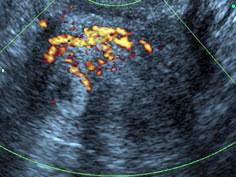

问题 27岁孕妇,孕8周时阴道出现无痛性出血, 血B-HCG为2200ul/ml,根据下图所示,最有可能诊断为 ( )

选项 A、子宫内膜异位症 B、子宫内膜息肉 C、输卵管壶腹部妊娠 D、子宫角妊娠 E、子宫肌瘤

答案 D